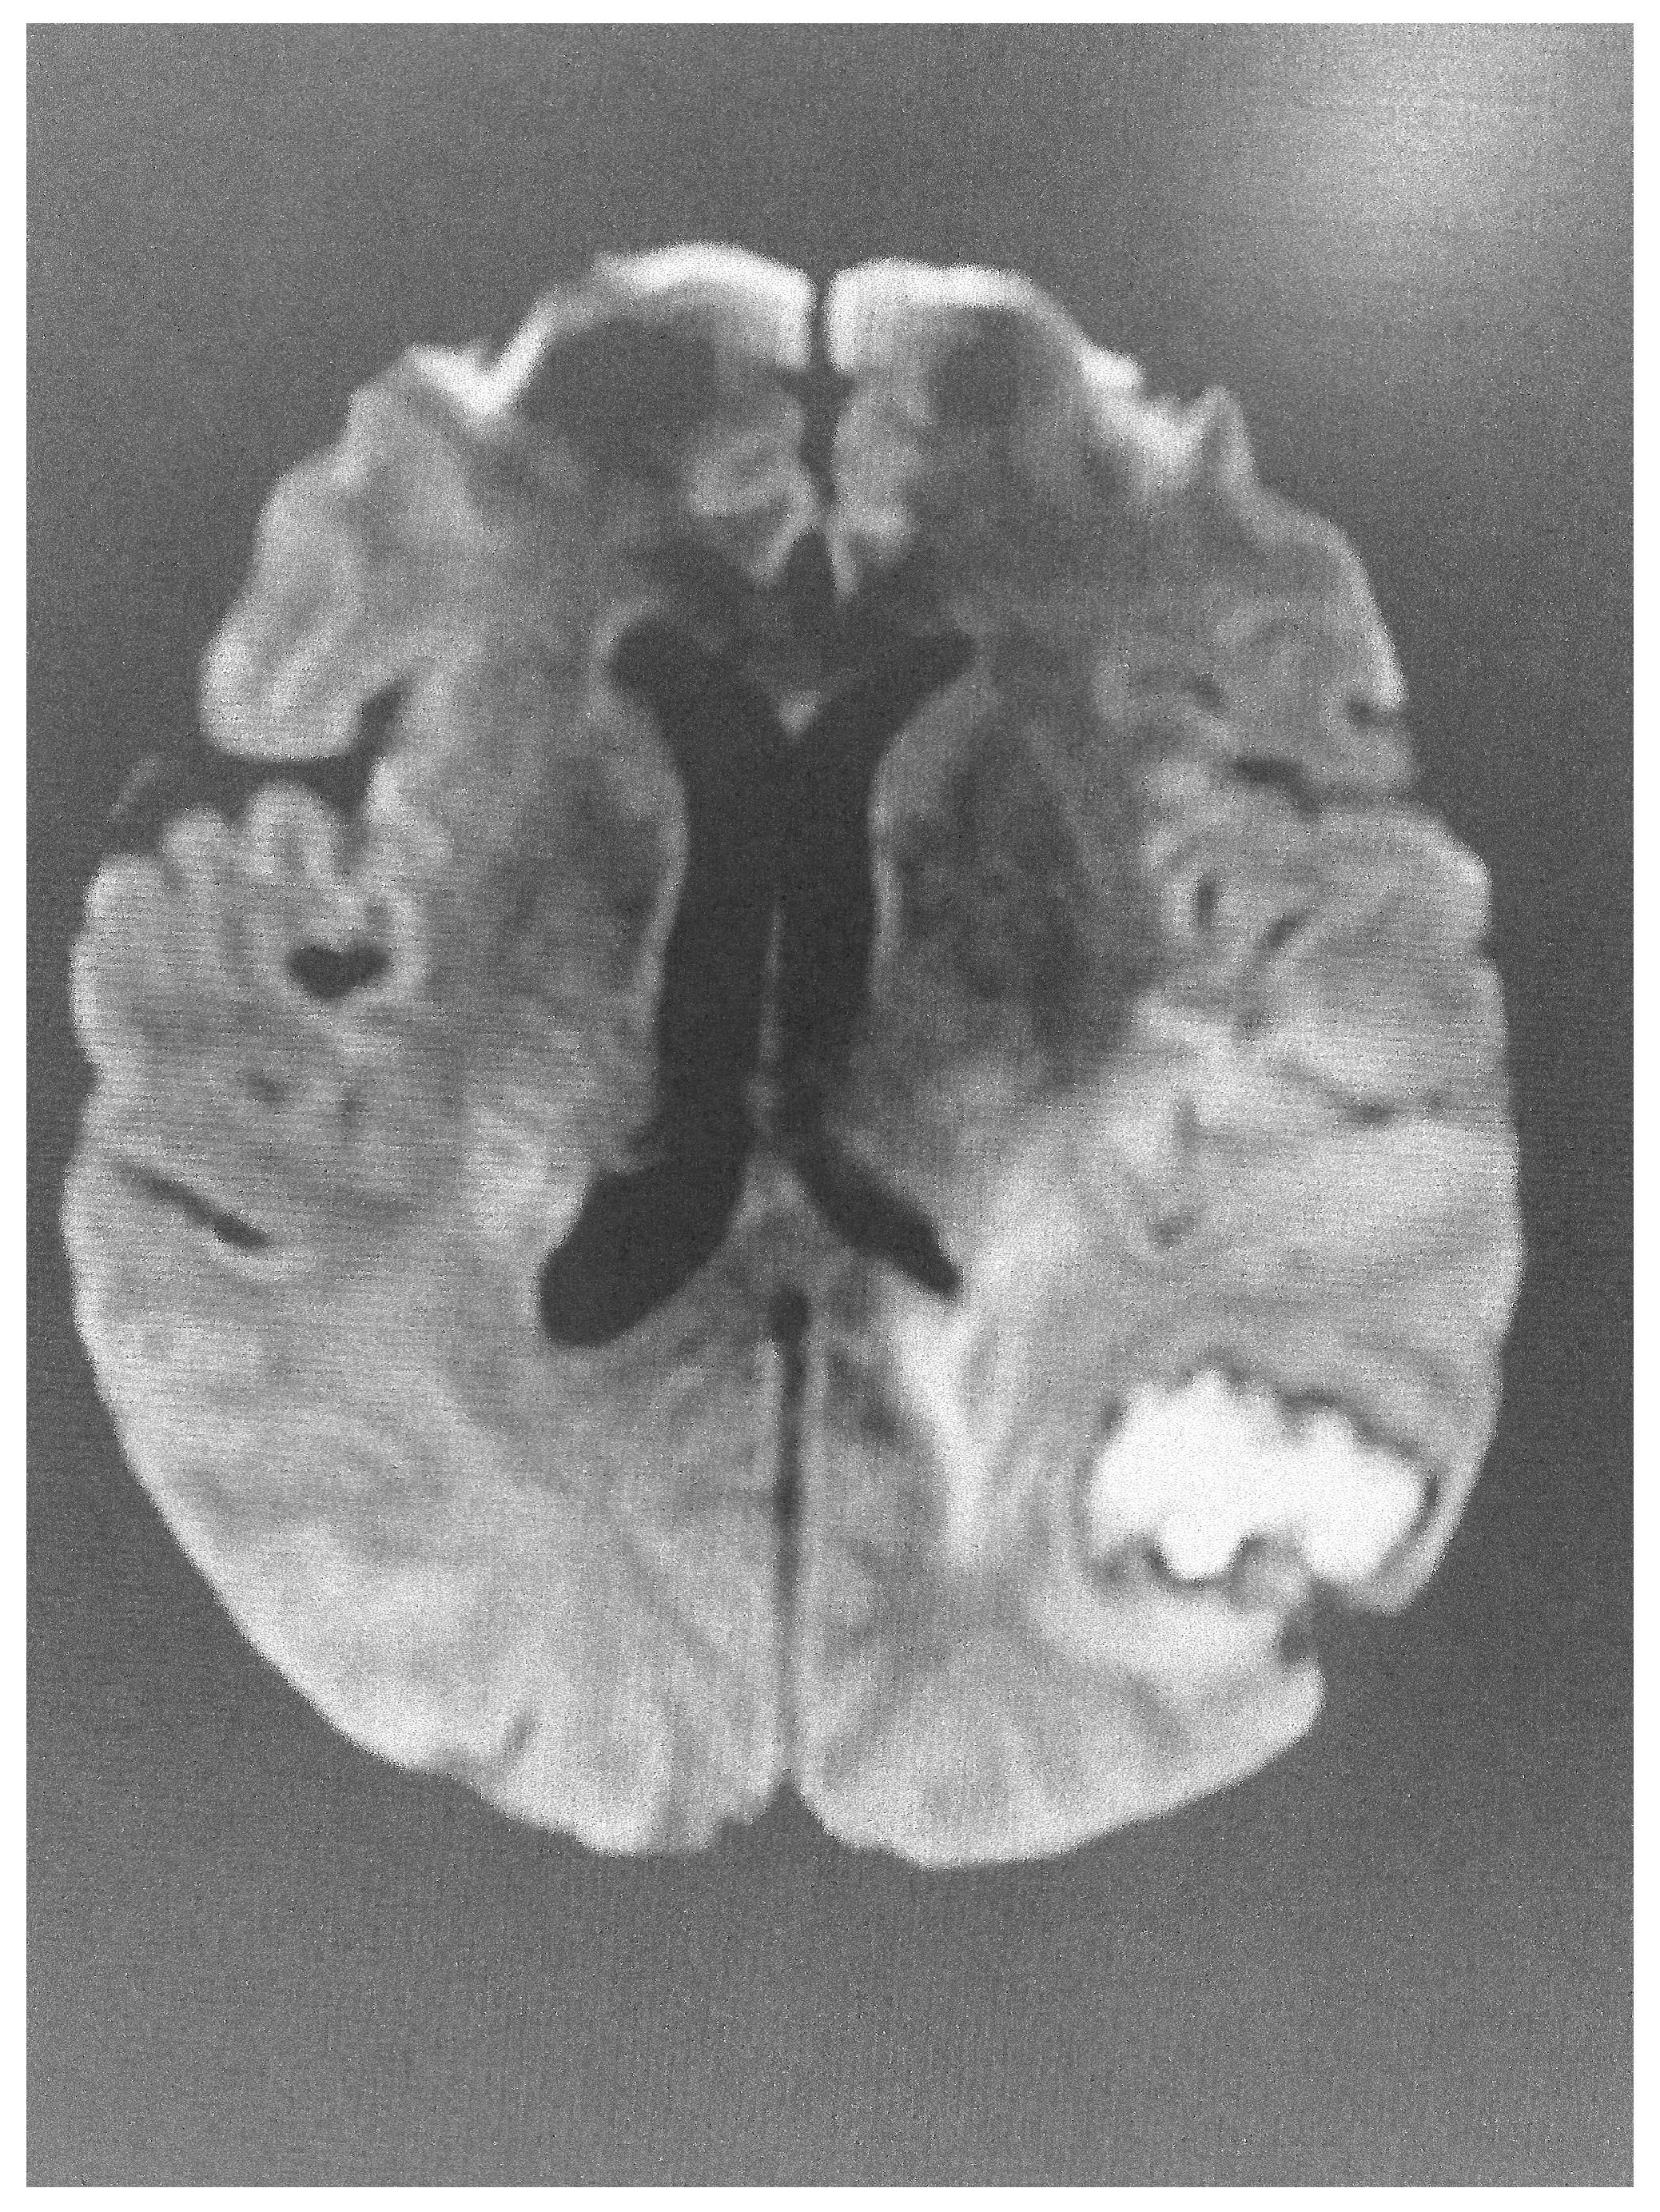

dMRI utilizes the anisotropic water diffusion in white matter to produce micro-architectural details of white matter tracts and provide information about white matter integrity [14]. Through dMRI, we can define the structural connectivity between various brain areas and perform a detailed mapping of the connectional pathways of the brain [15]. White matter connectivity differences were identified using dMRI in military personnel exposed to trauma with or without post-traumatic stress disorder [16]. Furthermore, repeated overstimulation of the stress system, caused by prolonged exposure to highly stressful experiences, may affect brain structure, cognitive function and mental health. According to UK Biobank data, there is a clear link between stress and changes in brain microstructure, impairment in cognitive function and negative mental health outcomes [17]. Sex plays a distinct role in this reaction. Females and males present significant differences in white matter integrity when exposed to low levels of early life stress, with females showing lower white matter integrity compared with males. No difference in white matter integrity is observed in males and females exposed to mild stress. However, males are more sensitive to early life stress, while females are more sensitive if early life stress is followed by stress in adult life [18]. Diffusion images have been also used to clarify the acuity of lesions identified using FLAIR imaging (Figure 1 and Figure 2).

Figure 1. Brain FLAIR image showing evidence of stroke.

Figure 2. Abnormal diffusion image of the brain in the same patient, indicative of acute lesion.